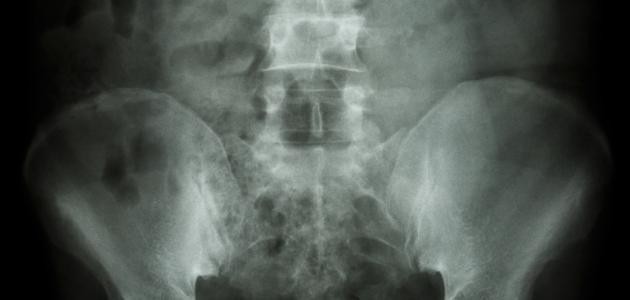

يُعتبر الكالسيوم أحد العناصر المُهمّة في جسم الإنسان، إذ إنّ ما نسبته 99% من الكالسيوم الذي يدخل الجسم ينتهي به المطاف مترسّباً في العظام والأسنان، أمّا النسبة المُتبقية فتبقى ذائبة في الدم، وقد يتعرّض الجسم لاضطراب مُعين يُخلّ بالتوازن ما بين الكالسيوم وعدد من العناصر الكيميائيّة المحدّدة في الجسم؛ ممّا قد ينتج عنه ترسّب الكالسيوم في أجزاء مختلفة من الجسم؛ بما في ذلك الشرايين، والكلى، والرئتين، والدماغ، ويُمكن تعريف التكلّس (بالإنجليزية: Calcification) على أنّه تراكم الكالسيوم بشكلٍ تدريجيّ في أنسجة الجسم، ممّا يؤدّي إلى تصلّبها، وقد تكون هذه العملية طبيعية أو غير طبيعية، وفي الحقيقة يُعتبر التكلّس مشكلة صحيّة في حال أثّر التكلّس في وظيفة أحد الأعضاء الحيويّة في الجسم، وفي بعض الأحيان قد يحدث اضطراب في مستوى الكالسيوم في الدم؛ ممّا يُشير إلى وجود اضطراب أيضيّ تتأثر فيه قدرة الجسم على استخدام الكالسيوم أو تنظيم مستوياته.

يتمّ تصنيف مشكلة التكلّس بناءً على العضو المتأثر بهذه الحالة من الجسم، وفي ما يأتي بيان لبعض هذه الأنواع:

- تكلّس الكلى: قد يؤدي حدوث التكلّس في الكلى إلى المُعاناة من تشكّل حصى الكِلى.

- الأنواع الأخرى: وتتمثل بحدوث التكلّس في صمّامات القلب، أو المفاصل والأوتار، أو العضلات، أو الدهون، أو المثانة، أو المرارة.